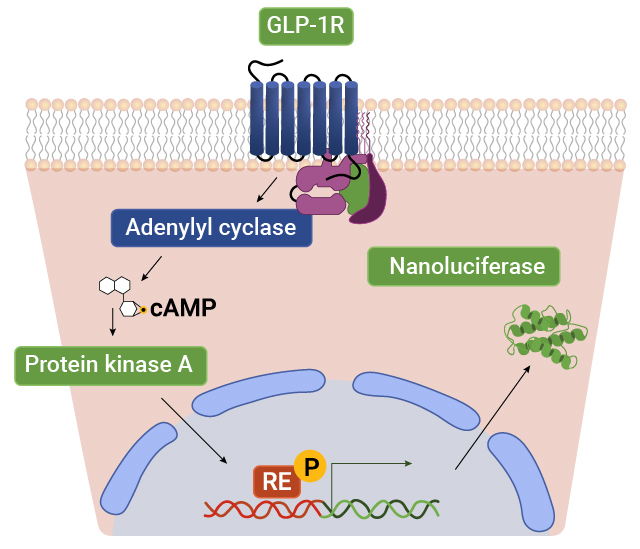

Measure GPCR Function With Bioassays

Our bioassays use engineered cells that couple receptor activation at the cell surface to a specific response element linked to a luciferase reporter. When a ligand binds to the receptor, intracellular signaling pathways are activated, driving the expression of luciferase. The resulting luminescent signal provides a sensitive, quantitative readout of receptor activity, enabling precise measurement of GPCR function and downstream signaling.

Contact our Tailored R&D Solutions Team about assays for GLP-1, GIP and glucagon receptors. We can even help you create a bioassay for your GPCR of interest!

Measure GPCR-Activated Transcription Factors With Reporter Vectors

GPCR signaling cascades result in activation of specific transcription factors that cause changes in gene expression. Response element luciferase reporter vectors allow the activity of specific GPCR-activated transcription factors to be measured using simple, sensitive add-mix-read assays.